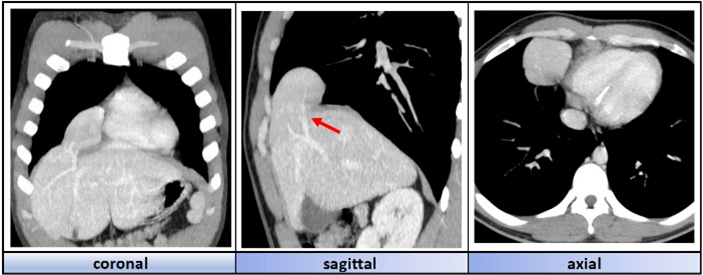

We present the case of a 21-year-old patient with no relevant past history who presents to the emergency room with episodes of mild chest pressure during physical exertion. A diagnostic study is performed, with the significant finding of a space-occupying lesion in the right lower mediastinum on the chest X-ray. To clarify the diagnosis, a thoraco-abdominal CT with contrast is requested, revealing a mass at the level of the lower right mediastinum compatible with accessory liver tissue dependent on segment VIII. It is associated with the presence of a diaphragmatic defect in the right parasternal space (Figure 1).

Figure 1: Tomography images of the different sectional planes in which we appreciate an intrathoracic accessory liver lobe dependant on segment VIII. Its vascular pedicle can be visualised (red arrow).